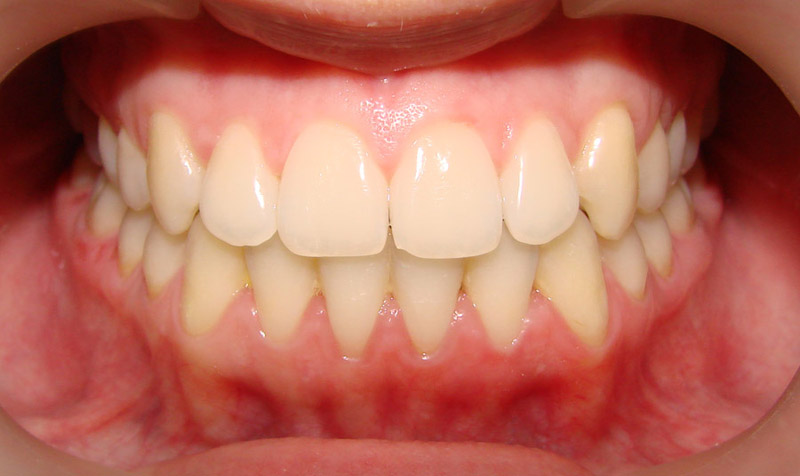

А это уже молодой человек 10 лет. Тоже получилось справиться без удаления. Хоть оно и было показано. Но мальчик очень упорно носил специальные аппаратики и резиночки. Покажу со всех сторон. Этот случай победил в конкурсе на конференции

Молодая девушка и очень мне нравится результат!